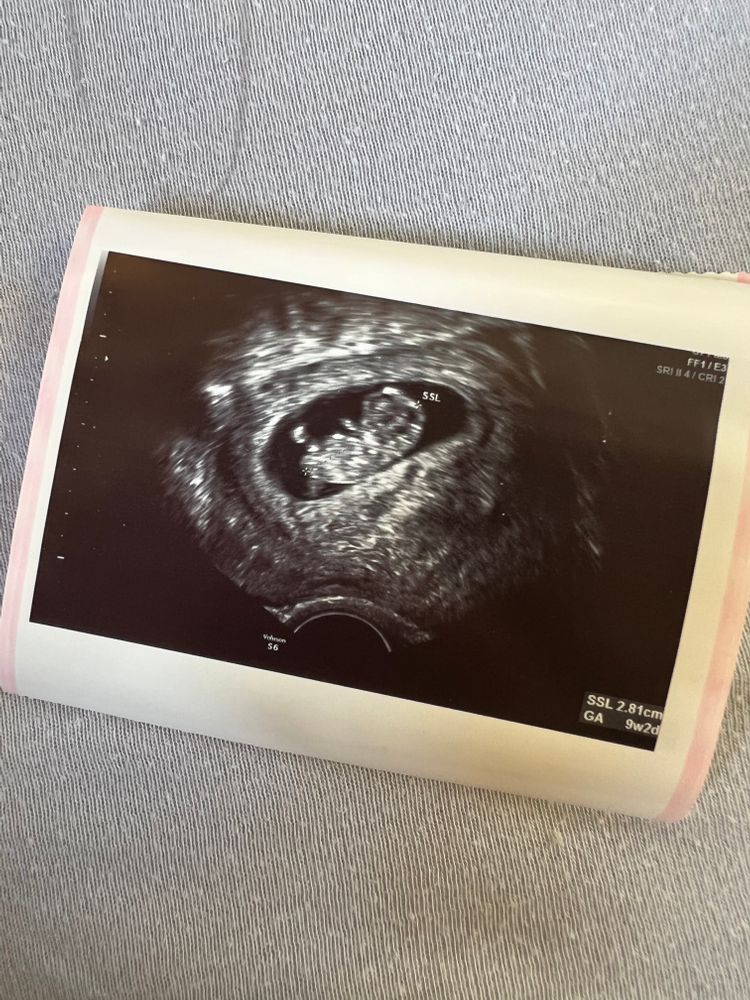

Почти закончился 6 месяц беременности а мне так и не могут сказать кто у меня родится. Через пару дней на узи, но не факт что скажут, старый аппарат и врач скорее не опытный. Я сейчас нахожусь на 25 неделе. Последнее фото было месяц назад на 21 неделе. На первом узи сказали что 80% мальчик(1фото). На втором узи сказали что ничего непонятно. На третьем сказали что возможно девочка, но ничего не видно. Помогите, пожалуйста, определить пол🐰